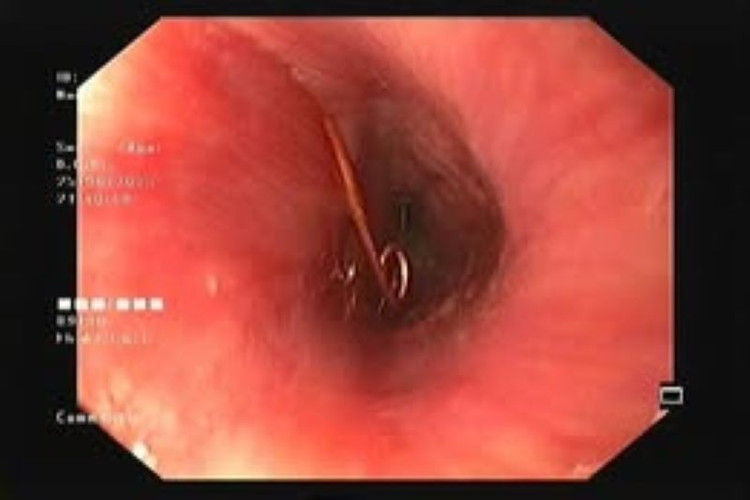

Tại Khoa Cấp cứu, qua thăm khám và hình ảnh nội soi, bác sĩ phát hiện cây kim băng dài khoảng 3 cm, đã bung ra thành hình chữ L và đầu nhọn đang ghim vào thành thực quản – gây nguy cơ thủng, chảy máu và nhiễm trùng rất cao.

Thực hiện nội soi lấy kim băng dài và nhọn kẹt trong lòng thực quản bé trai ra ngoài - Ảnh BVCC